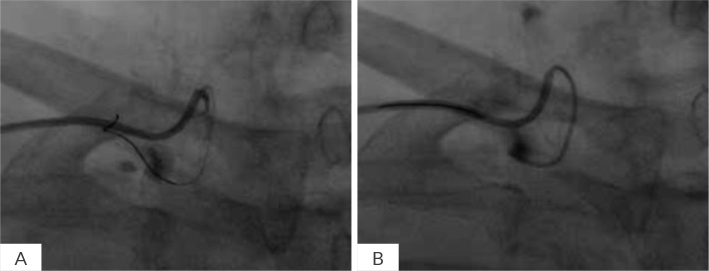

Case description: This report highlights three cases of perforated artery managed with coil embolization. The first case involved perforation of a small branch of the internal mammary artery, the second a ruptured aneurysm in the superior mesenteric artery and the third a distal branch perforation of the diagonal artery. All patients presented with significant haemorrhage, requiring urgent intervention. Coil embolization was successfully performed in all cases, achieving haemostasis and preventing further complications.